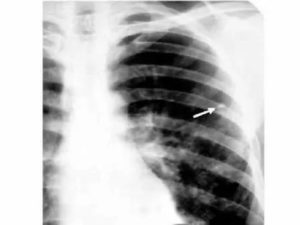

При рентгенологических исследованиях очаг Гона представляет собой затемнение овальной (реже округлой) формы с резкими очертаниями, размерами до 5 мм. Образования могут быть единичными и множественными. Излюбленная их локализация – нижние и средние отделы легких. Иногда контуры очага могут быть неровные. Легочный рисунок неизменен, корень не расширен.

На разных этапах петрификации (обызвествления) очага Гона изменяется, структура его может быть:

- гомогенной (однородной),

- негомогенной: имеет зернистое или дольчатое строение, неровные границы.